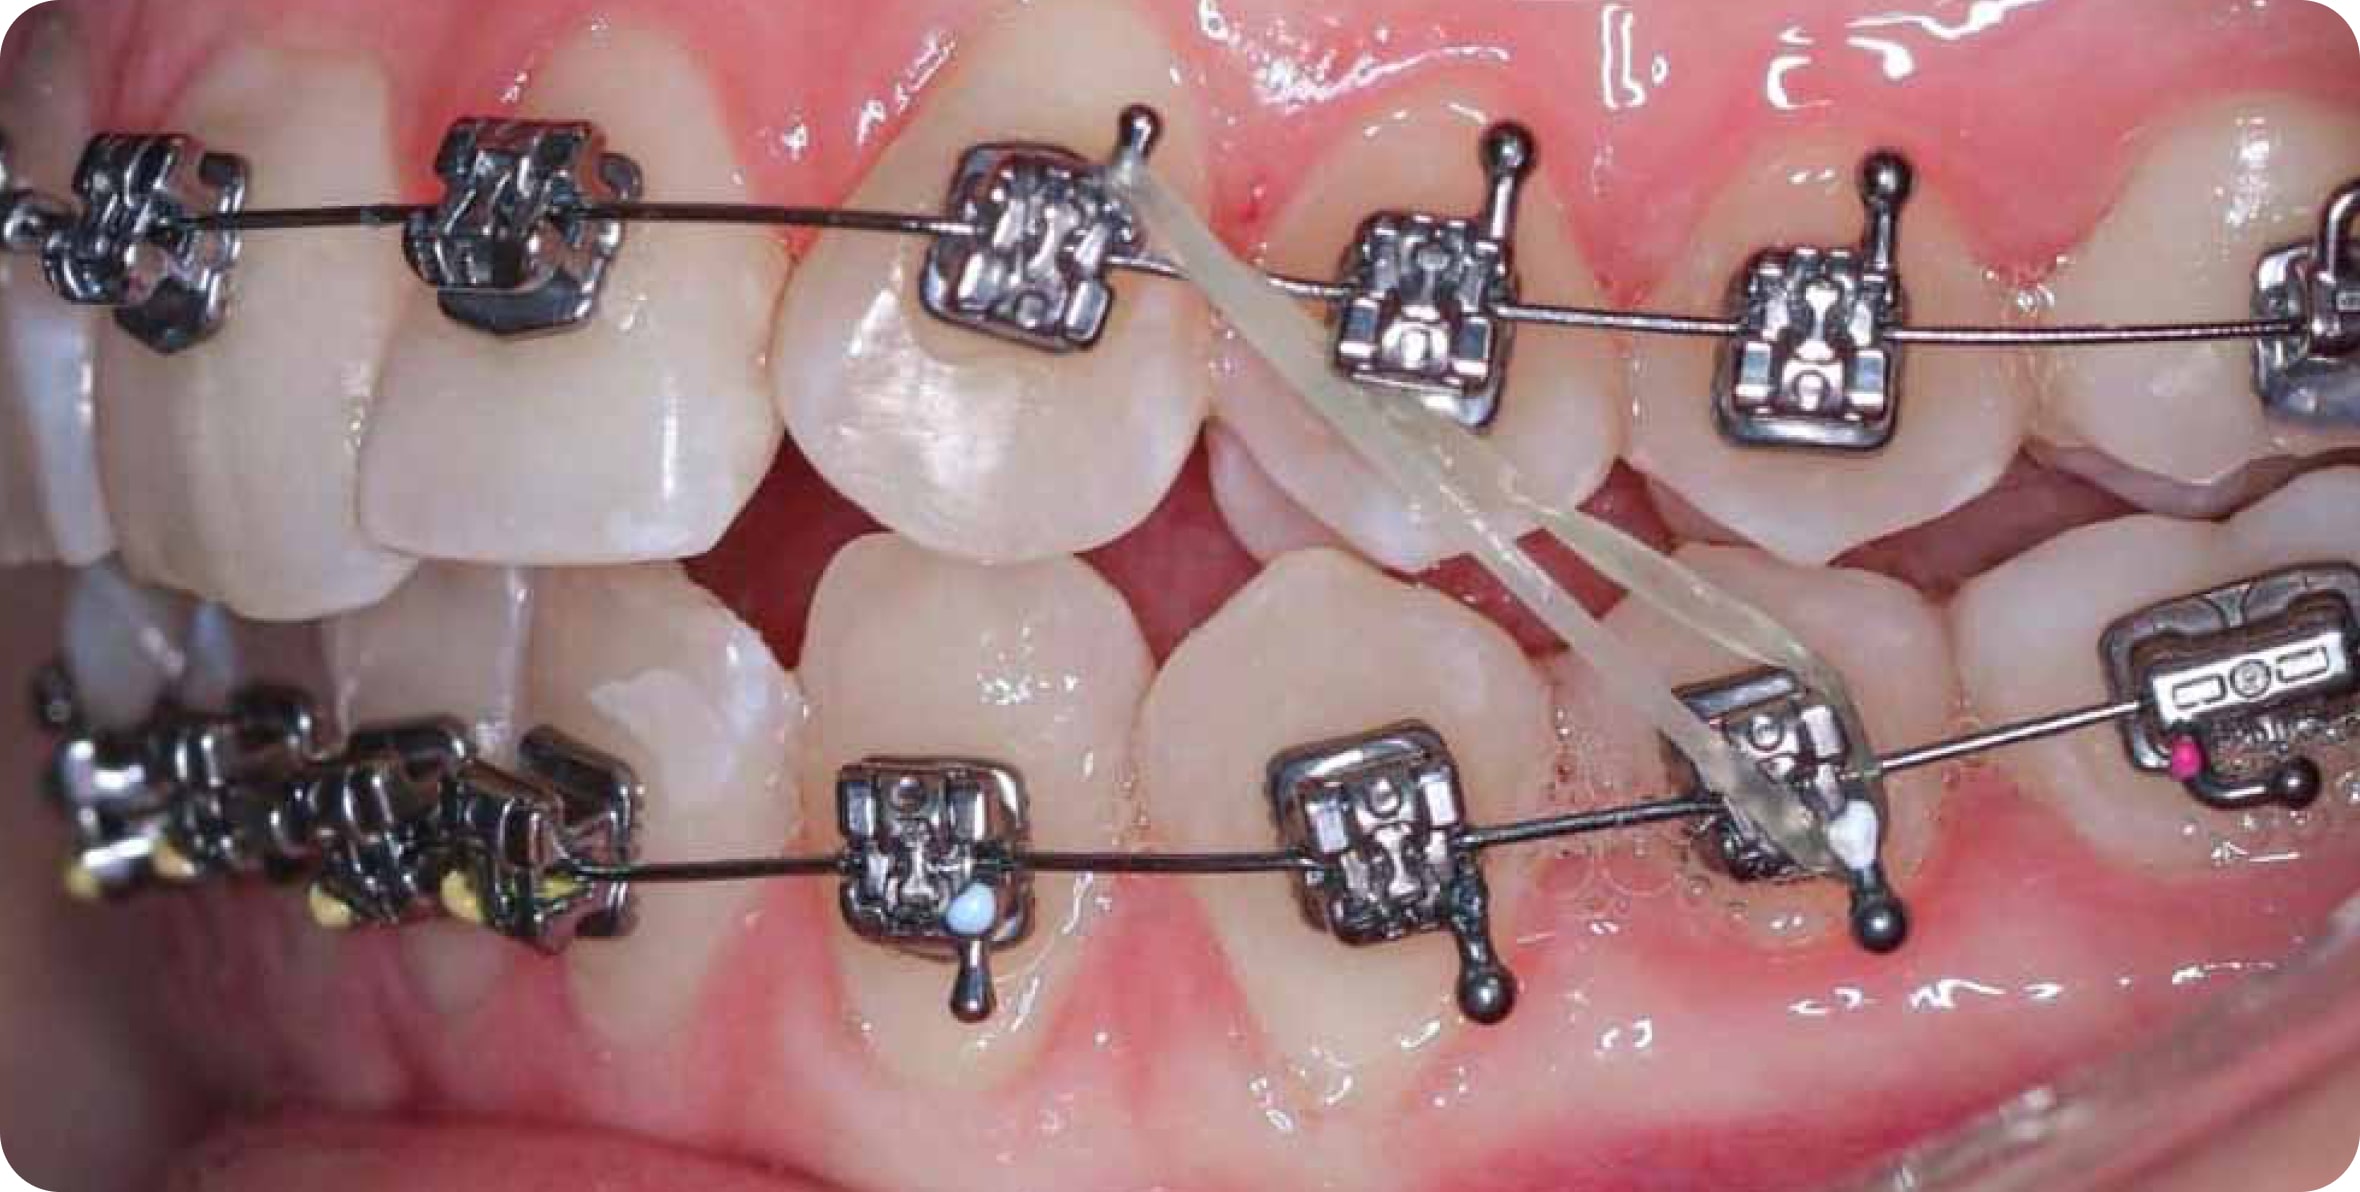

• Часто с брекетами применяют допольнительные элементы: мини-винты, эластики, кнопки, цепочки

Что за резинки на брекетах?

Специальные резинки между брекетов - эластики - помогают зубам быстрее перемещаться в нужном направлении. Используются не во всех случаях

Что за резинки на брекетах